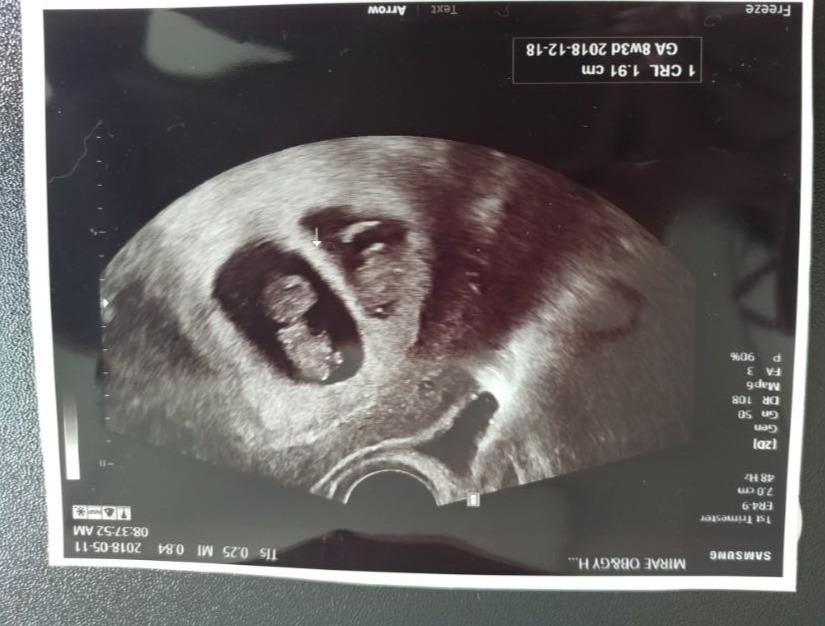

룰루&랄라. 랄라는 늘 초음파 카메라로 엄마를 또렷하게 쳐다본다. 룰루는 엄마가 TV볼 때처럼 항상 같은 자세로 눕방이다.